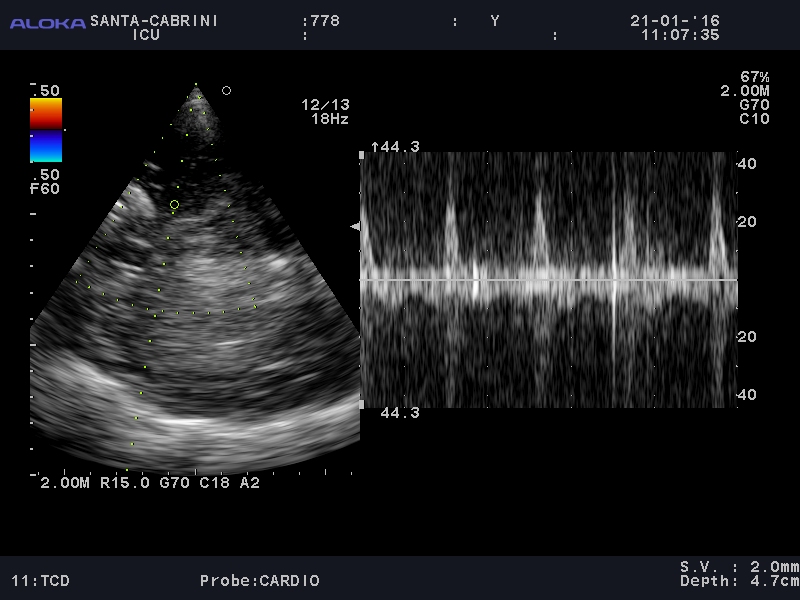

Next the TCD waveform (from the left temporal area):

It was fairly difficult to find a good vessel, and likely at a bifurcation hence a narrow and bidirectional spike on doppler. The signal noise made it difficult to look clearly at diastolic flow and make a definitive call of circulatory arrest.